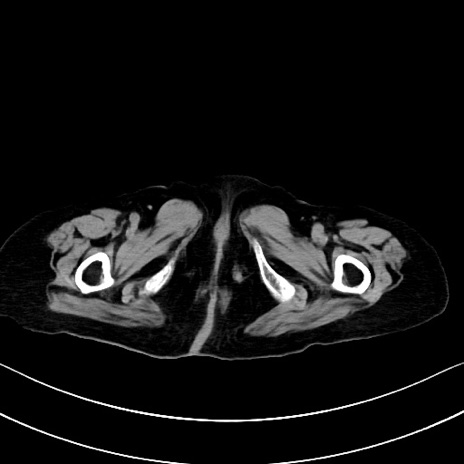

横断像